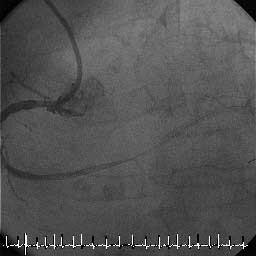

Fig5 1クールcutしたあと、IVUS前の造影です。これだけ考えたのに、LCxはdelay

となってしまいました(残念)。ここで、気にせずLADをもっと削る、いったんワイ

ヤをLCxに入れ替えてLCxを削る、といった選択もありますが、以前、あるライブで

LADのDCA中にD1が閉塞し、それを拾いなおすのにその道のプロの先生が大変ご苦労さ

れていたのを思い出し、ヘタレの私はステントに移行することにしました。

Fig.5